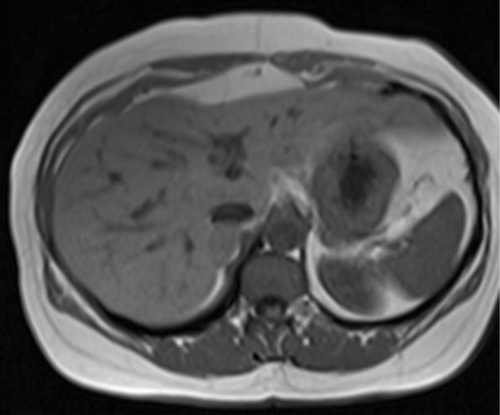

Case 5

A 45-year-old male is found to have an incidental right adrenal lesion on CT. An MRI was arranged for further evaluation.

1. What sequences are shown?

2. Describe the findings.

3. What is the likely diagnosis?

- T1 weighted axial MRI in-phase and out-of-phase. Fluid is dark on T1 images, and the cerebrospinal fluid (CSF) in the spinal canal is seen to be dark. When assessing for the type of sequence, looking at vessels can be misleading as they are usually dark due to flow void.

- There is a well-defined nodule seen in the right adrenal gland. It appears solid on the in-phase image and demonstrates complete loss of signal on out-of-phase image.

- The diagnosis is an adrenal adenoma. Loss of signal on out-of-phase imaging is due to chemical shift artefact, caused by the composition of the lesion. An adenoma contains intracellular fat, which causes the loss of signal. It is not composed of macroscopic fat, otherwise it would be bright on both T1 and T2 MRI.